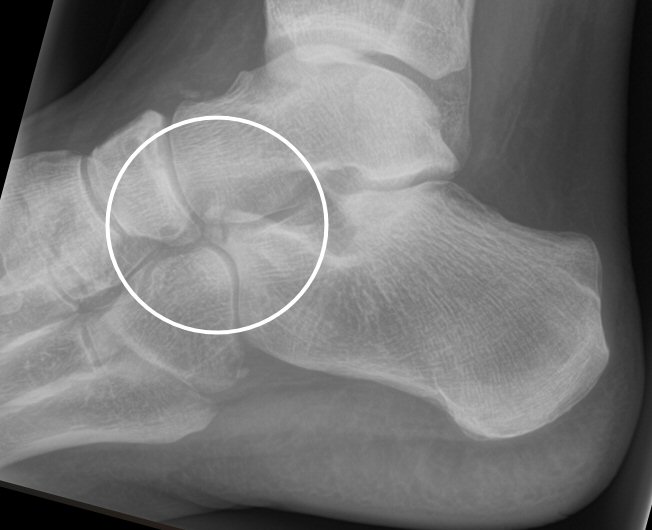

Fraktur i proc. anterior calcanei